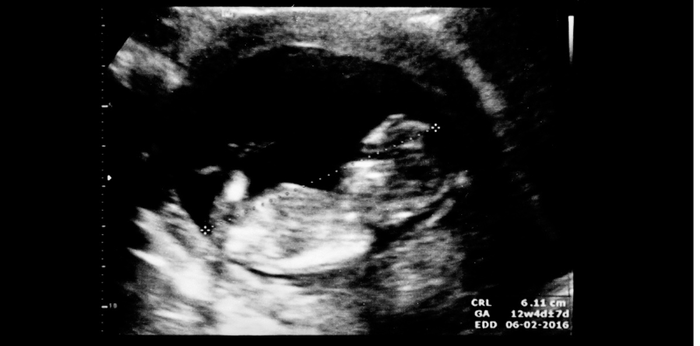

Fetal movement is an important movement for monitoring the health and growth of the fetus. The baby will start to show movement periodically after the baby’s nervous system and muscles have developed and matured sufficiently. Generally, it starts to learn to move around in the fourth month of pregnancy. This movement is a signal that helps the mother to be aware of the growth and health of the baby more easily.

Pregnancy 18-20 weeks

- It feels like wings are flapping or hiccups.

- Feel it lightly

Pregnancy 20-24 weeks

- I felt the movement and stretching of my arms and legs more clearly.

- You may feel a nudge, roll, or spin.